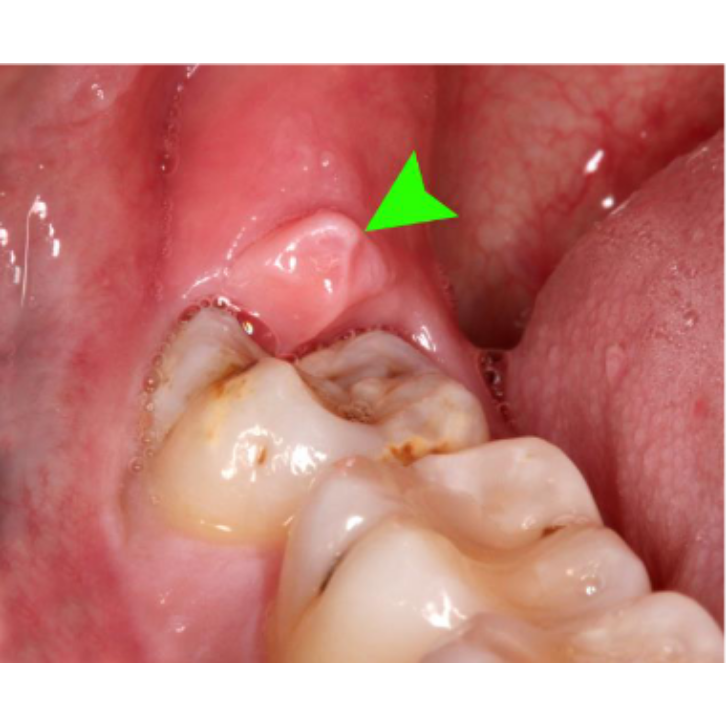

wisdom teeth removal best clinic ss multispeality dental centre in pudur chennai

Wisdom teeth removal specialists Chennai

Best multispeciality dental centre Pudur Chennai

Wisdom teeth removal clinic Pudhur Chennai